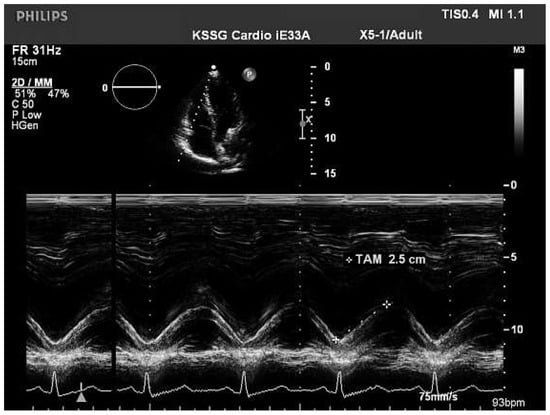

Assessment of the right ventricular function in M-mode (tricuspid annular excursion, RV outflow fractional shortening)